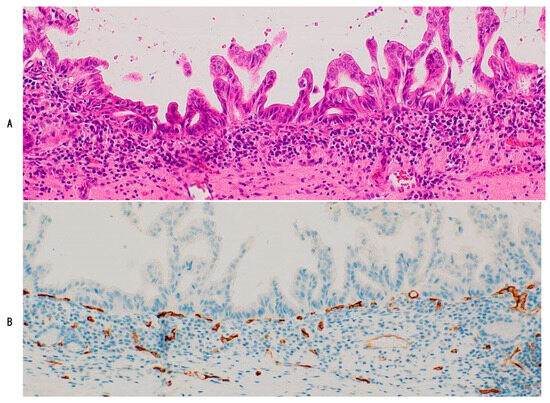

In the remaining half of IPNBs and two-thirds of ICPNs, capillaries were sparse in the intraluminal neoplastic components [10,11] and were absent or barely identifiable in some regions or areas (Figure 5A,B). These intraluminal epithelial neoplastic components showed histological features of type 2 IPNB and ICPN (Table 3) [8,9,20]. One possible explanation for the development of such less-capillarized lesions is that the growth speed of neoplastic epithelial cells might have been much faster and that PCP-like capillaries could not catch up with the speed of neoplastic growth. Another possibility is that neoplastic growth of type 2 IPNB and ICPN does not require an oxygenated capillary blood supply but may rely on anaerobic metabolism for their energy acquisition.

Figure 5.

Capillaries are sparse in the intraluminal component, showing solid or cribriform growth (right to center), while regular and dotted capillaries are found in the stalks of papillary neoplasms in other areas (left) in the same case. Intraductal papillary neoplasm of bile duct (IPNB) (type 2) of intestinal subtype with foci of type 1 IPNB areas. (A), HE; and (B), CD34 immunostaining.

Interestingly, type 2 IPNB or ICPN with sparse capillaries not infrequently contained variable-sized neoplastic areas or components with regular and dense capillaries and type 1 histology (Figure 5A,B), suggesting that type 1 IPNB and ICPN with dense capillaries might have transitioned to type 2 IPNB and ICPN with sparse capillaries [11,12]. Therefore, such a sparse capillary pattern may have developed along with overt malignant transformation of neoplastic epithelial changes in type 1 IPNB and ICPN. Dotted capillaries were regularly distributed in the stalks and intervening stroma in all the PGAs. PGA with invasive carcinoma is not discussed here because of the absence of such cases in our cohort.